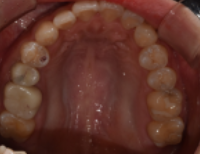

수술 후의 사진입니다. 가장 먼저 임플란트에서 치아의 '기둥' 역할을 하는 픽스처를 식립하였고, 그 후 지주대, 인공치근까지 치료가 완료되었습니다.

기존에 교체가 필요한 골드크라운도 올 세라믹 크라운으로 함께 진행하여 저작 능력과 심미성 두 마리의 토끼를 다 잡는 방향으로 치료가 진행되었습니다.

치료 전, 후 사진입니다. 같이 보니 확연한 차이가 느껴지시죠?

치료를 받으신 환자분도 너무 만족해하셔서, 저 역시 매우 흡족했던 치료였습니다. 며칠 전에도 내원하셔서 정기검진을 받고 가셨는데요.

'이제 음식 먹을 때 불편감이 전혀 없습니다. 제 자연치아 같아요.^^'라는 말씀도 해주셔서 웃으면서 검진을 완료했습니다.